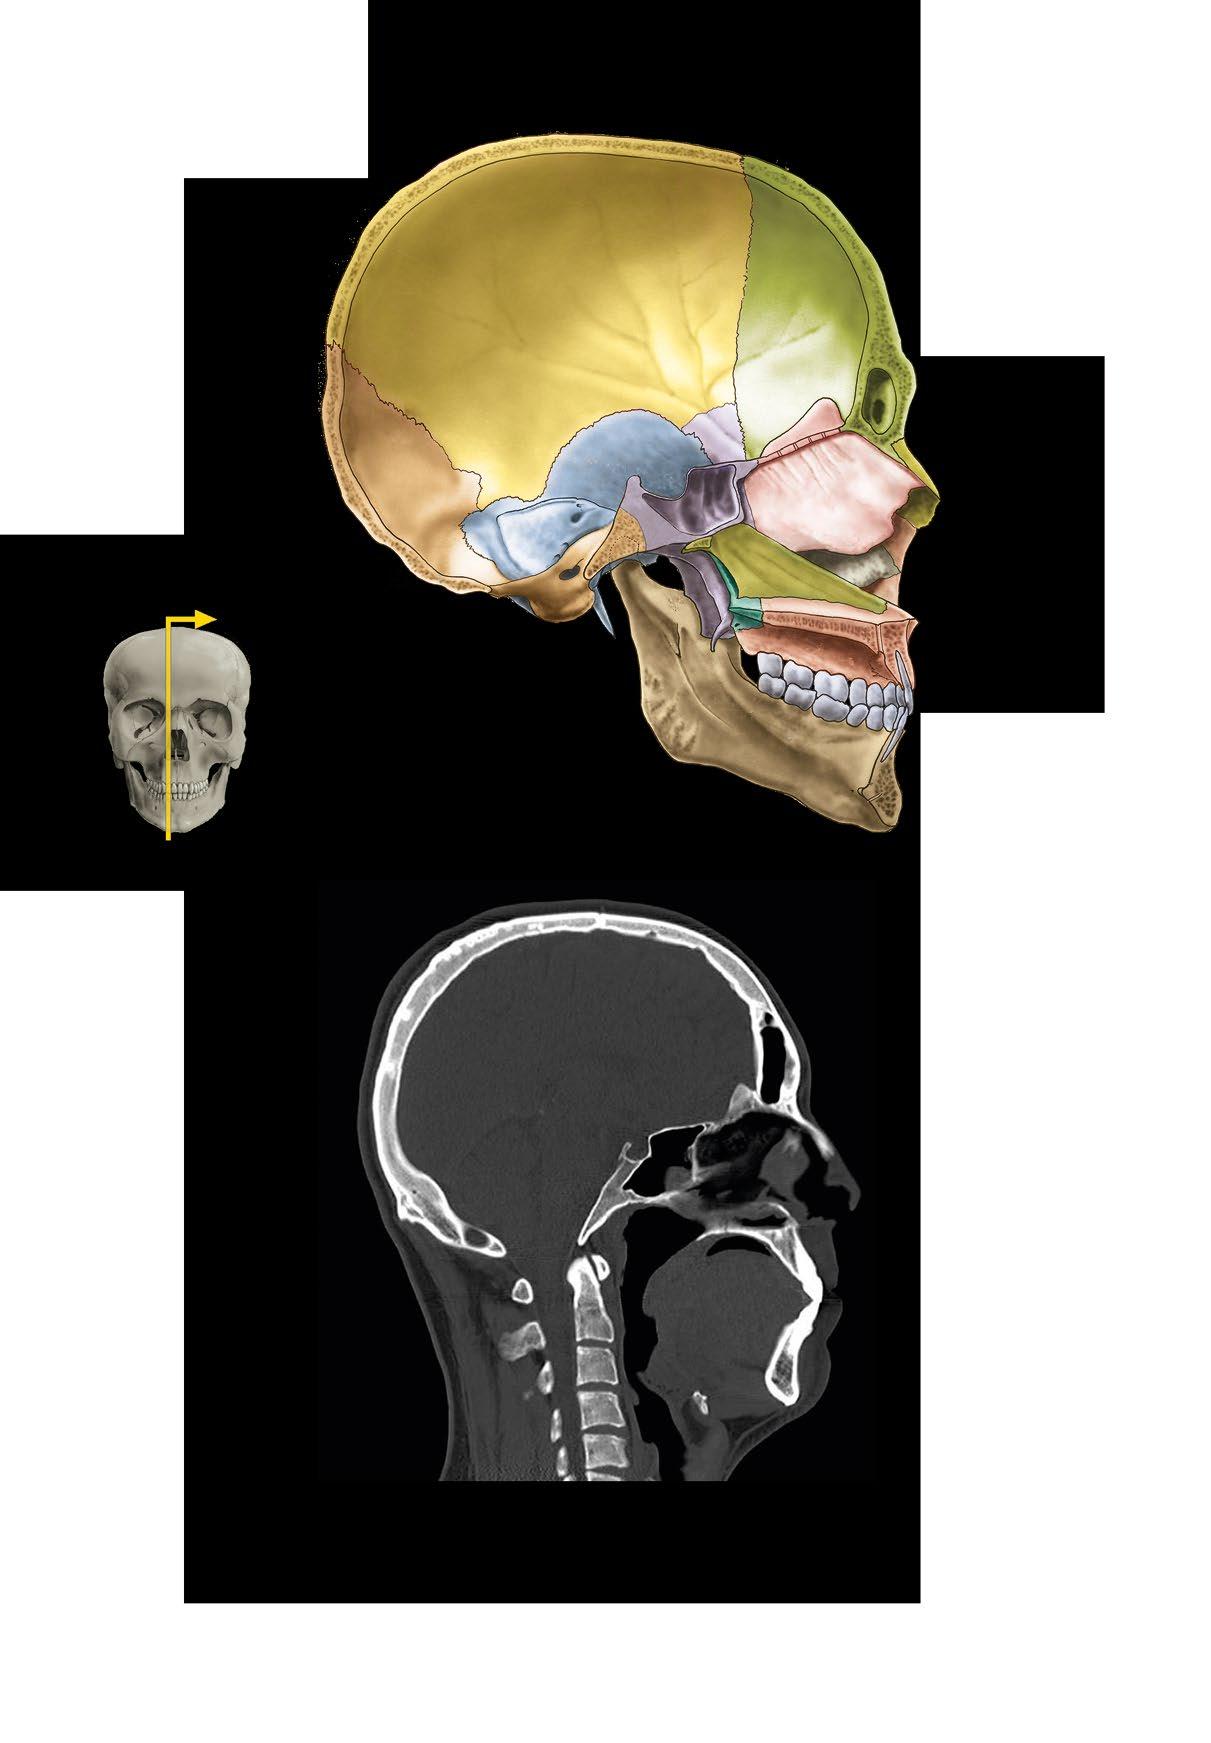

a Sagitální řez lebkou b CT lebky v sagitální rovině

os sphenoidale

os palatinum

maxilla

sella turcica sinus sphenoidalis

os nasale lamina perpendicularis ossis ethmoidalis/ septum nasi

concha nasalis inferior vomer

praemaxilla

sinus frontalis

pharynx

mandibula os hyoideum

a Sagittal section of the skull b CT of the skull in sagittal plane

sutura coronalis

os frontale

arcus superciliaris

os nasale

canalis opticus

ala major

foramen zygomaticofaciale

foramen infraorbitale

apertura piriformis

spina nasalis anterior

glabella os zygomaticum

foramen frontale

ala major ossis sphenoidalis